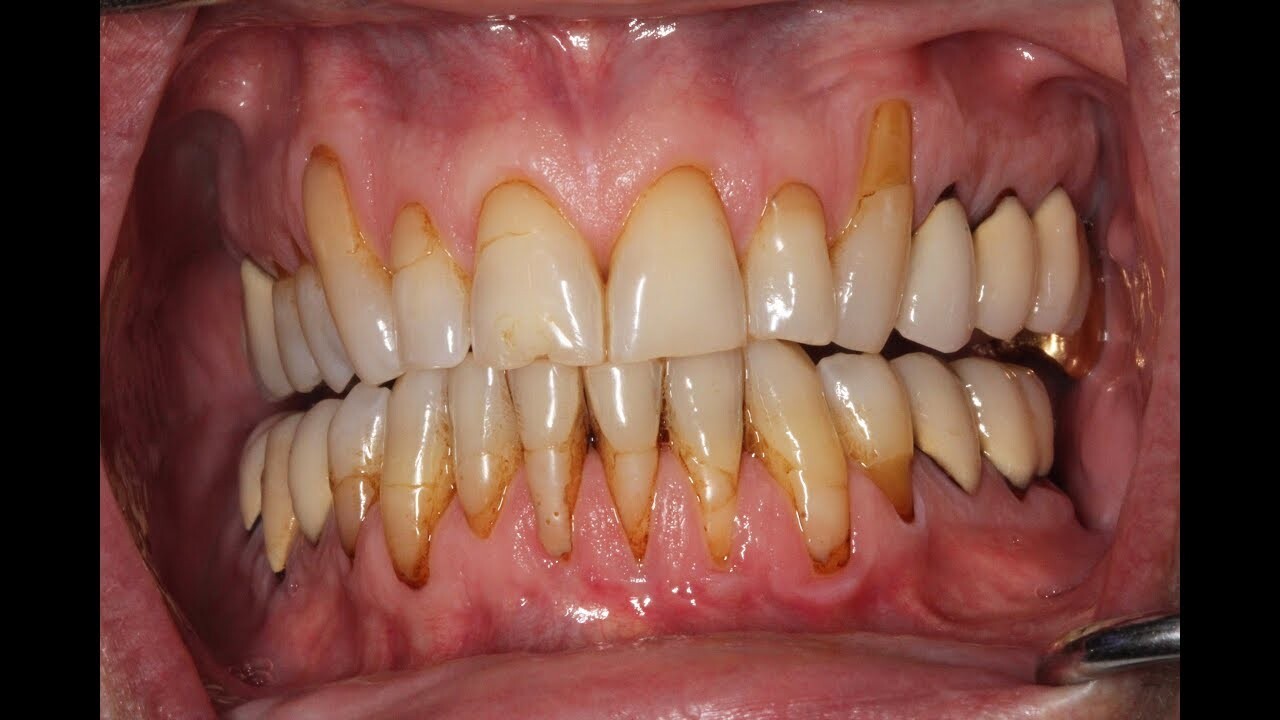

Yes, dentists can tell if you vape by looking for signs of it in the mouth. These include dryness or inflammation of the gums, discoloration, and a burning sensation when oral tissues are touched or probed. Additionally, the chemicals found in e-cigarette liquids will leave a specific residue on surfaces like teeth and tongue that can be observed during an examination and on the inside of your cheeks and lips. Additionally, if you vape too often, there may also be a noticeable discolouration in the teeth which will give away that you are a regular vaper. However, even if these signs are present it does not necessarily mean that you have gum disease. It is important to continue to practice good oral hygiene and seek regular check-ups with your dentist to ensure that any issues are caught as early as possible.